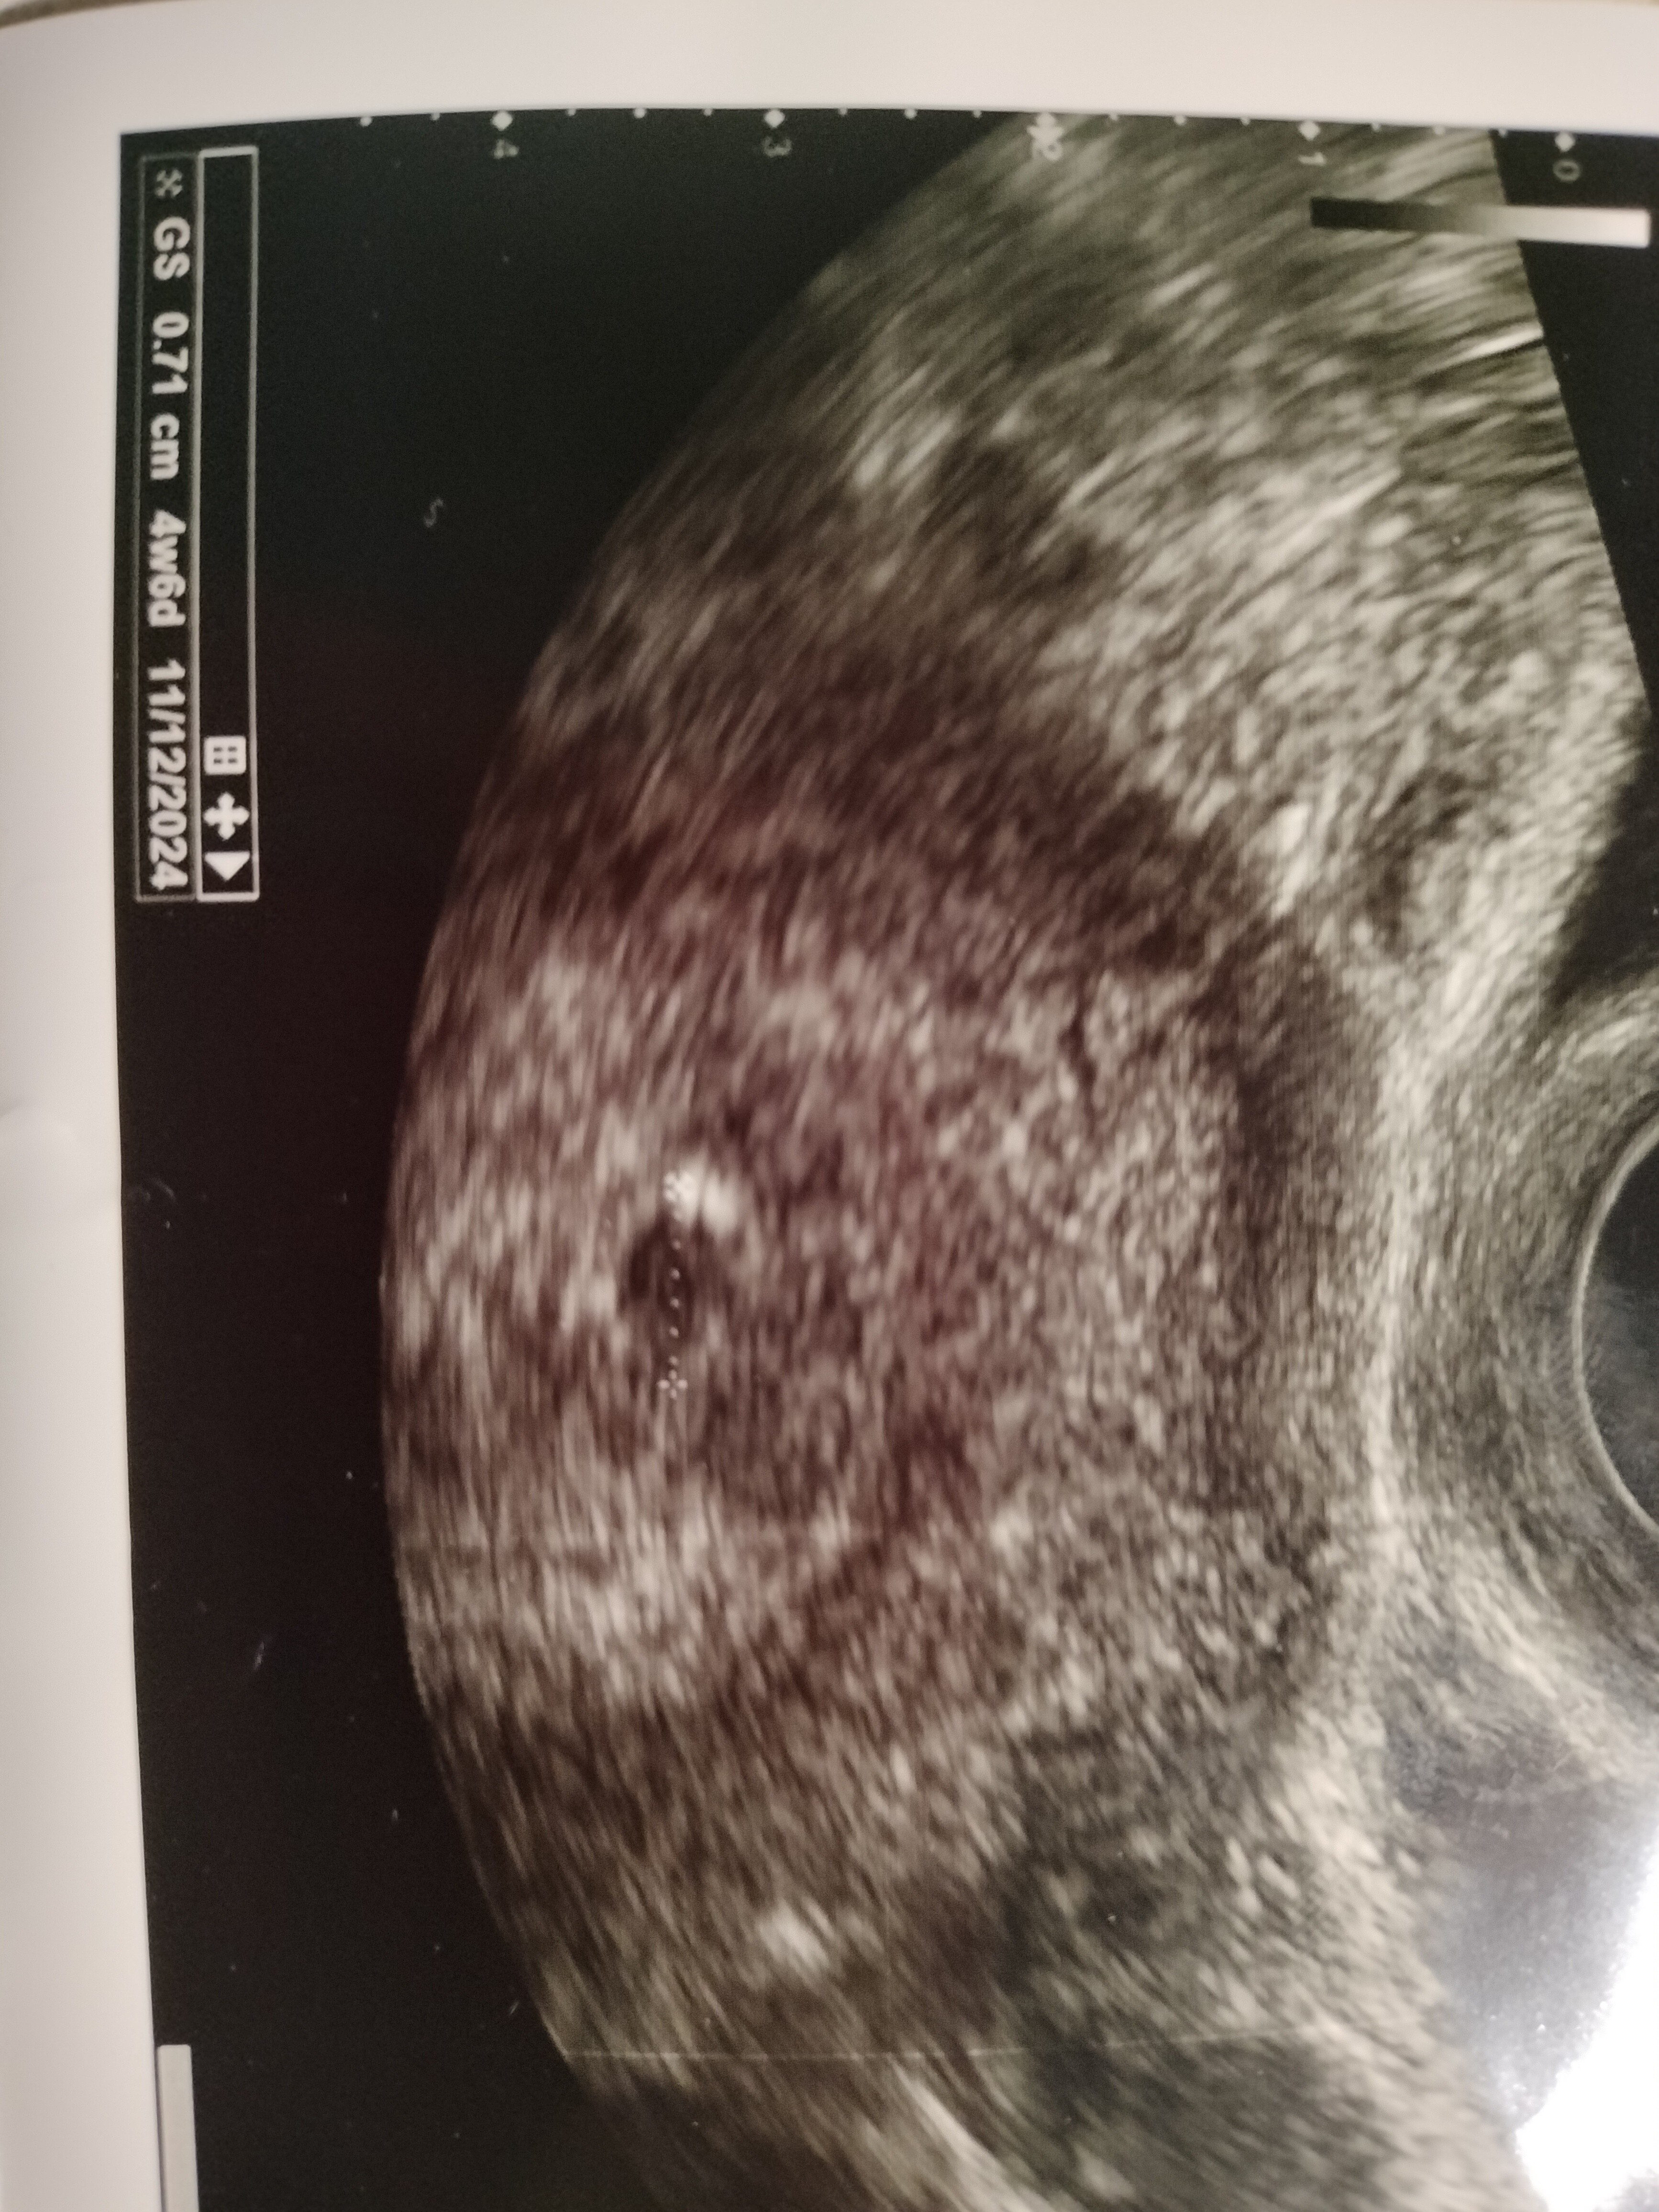

Ja dziś po kolejnym USG, już coś widać, zarodek się szykuje. Z OM 6+1 jednakże z USG 4+3. Także z USG bardziej wiarygodne, bo gdy miałam ostatnia miesiączkę to jeszcze była antykoncepcja, dopiero 14.03 wyciągałam wkładkę. Więc się zgadza że poszło odrazu i 4 tyg.